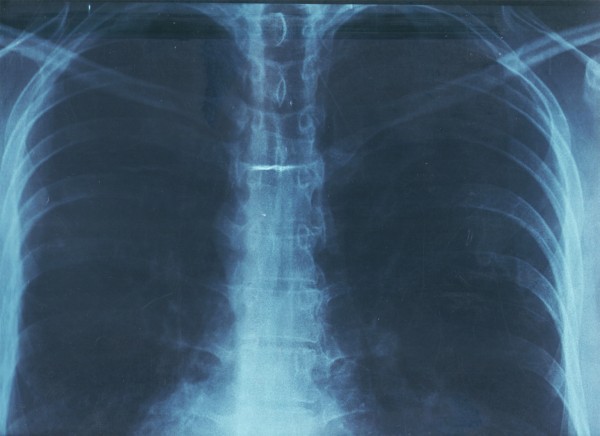

El vacío existencial es un término que, bajo la lógica precedente, se considera dentro de la dimensión de lo real. El objetivo de esta propuesta es identificar el vacío existencial en el cuerpo a través de un escaneo por rayos X del tórax (imagen 4). El vacío se define como un sin sentido de la vida, una insatisfacción persistente y una realidad insoportable.

La imagen cuatro fue generada mediante una técnica de diagnóstico médico de rayos x. Se sometió a un proceso de escaneo en alta resolución y se editó para acentuar sus elementos mediante una corrección de color en un editor de imagen digital. Se usó este método porque la radiografía en película necesita de una fuente de luz para identificar sus elementos; al escanearla, es más fácil visualizar los detalles.

Se aplicaron diez filtros de color, aumentando el brillo y el contraste. Las imágenes 4, 5 y 6 fueron las que reconocieron más elementos. La imagen en azul muestra la matriz impregnada por los rayos gamma que atraviesan los tejidos de los pulmones y el corazón, registrando el vacío: lo único que se percibe son las vértebras dorsales, las costillas y parte de lo que (se supone) son las escápulas. En la imagen 5 se observa un enmarañado tejido en la parte central baja que acompaña a las vértebras cerca del estómago. Esta región se acerca demasiado a la estética computacional de arte generativo y se reafirma la trascodicficación de patrones provenientes de la naturaleza, en este caso del cuerpo humano.

Por último, la imagen número 6 muestra el vacío existente en el tórax y explica lo real a partir de una construcción ideal imposible, ya que la caja toráxica no muestra órganos ni tejidos, registra algunas texturas de color blanco pegadas a las vertebras. En la mayor parte del centro del pecho se registró el color negro como ausencia.

Las imágenes resultantes tienen como finalidad ser un proceso alterno de creación de imágenes en CG-art que no representan, presentan el fenómeno de estudio. Existe el dolor como síntoma en la dimensión de lo real. Estas imágenes podrían mostrarnos un atisbo del vacío existencial ocultado en la realidad, es evidente antenuestros ojos y oculto al mismo tiempo: ceguera episté- mica de la condición humana.